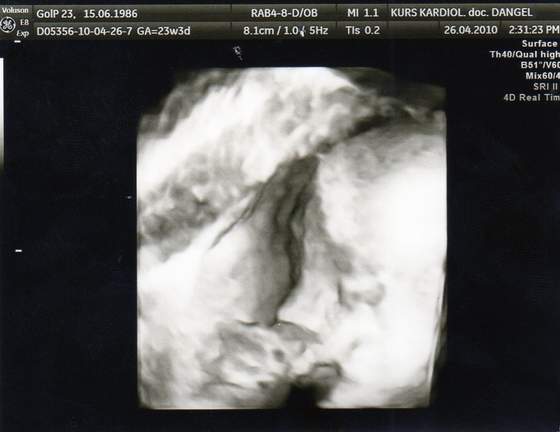

dziewczynki przesliczne dzieciaczki

ja usg mam co 4 tyg.jak idę na wizytę i zawsze jakąś fotkę dostanęwtedy mam porównanie jak mój maluszek rośnie!